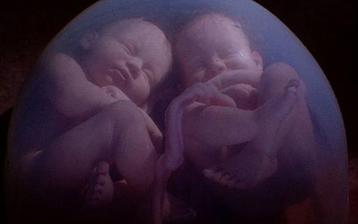

Jak asi víte, těhotenství je členěné na tři časové úseky, kterým říkáme trimestry – každý z nich trvá tři měsíce. Každý z trimestrů je zcela specifický, probíhají v něm určité charakteristické změny, podstupuje se vyšetření a nesou s sebou jiné pocity a obavy nastávající maminky.

- II. trimestr = 13. - 28. týden těhotenství

zázrak lidské života na videu